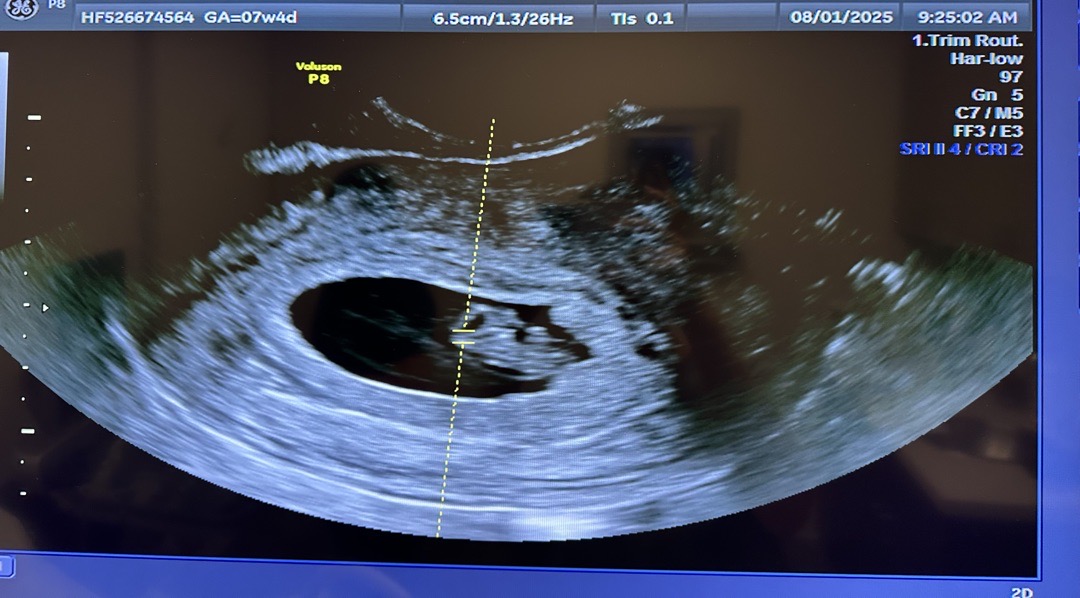

7주 4일 초음파 보고왔어요!

6주에초반에 갈색혈이 나와서 너무 걱정되는 마음에 바로병원가서 초음파 봤을땐 0.61cm에 그냥 길쭉한 모양에 심장소리도 너무 작아서 거의 못들었거든요! 그 후로 열심히 처방받은 질정 넣었더니 피비침은 다행히도 멈 췄어요. 기대반+ 걱정반 마음으로 오늘 초음파 보고왔 는데 이제 몬가 좀더 통통?해진 애기와 우렁찬 심소 들었더니 너무 마음이 놓여요!!ㅎㅎ휴ㅠㅠ 피고임도 쪼오금 작아진거같더라구요. 그 사이에 아기는 1.57센티 까지자라서 크기 주수로는 8주라고 하더라 구요 ㅎ그래서 자꾸 배가 아팠나봐요. 피비침 초반에 있으셨던 분들 넘 걱정마시구 애기를 믿고 기다 리면 그새 많이 커있을거에요!!